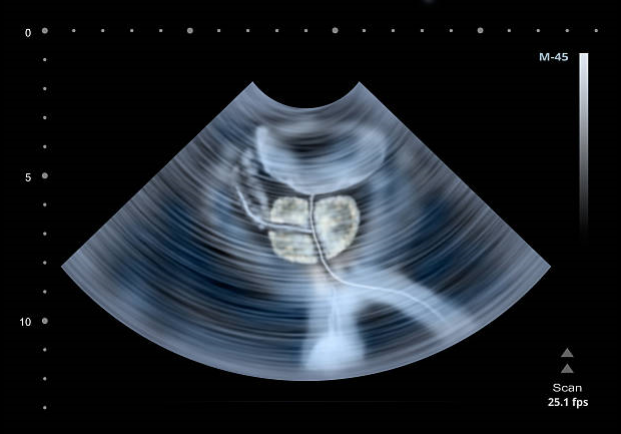

배꼽 바로 아래에 위치한 사과 모양의 기관으로 남성 생식기의 요로에서 중요한 역할을 하는 전립선은 사정 조절을 돕고 정자의 이동과 영양을 가능하게 하는 전립선액을 생성합니다. 또한 방광과 골반저 근육 및 경화증 근육과 같은 주변 근육을 지원합니다. 그러나 암은 전립선에도 생길 수 있으므로 전립선암의 초기 징후와 증상을 알아두는 것이 중요합니다. 그래서 이번에는 전립선암 초기증상에 대하여 자세히 알아보도록 하겠습니다.